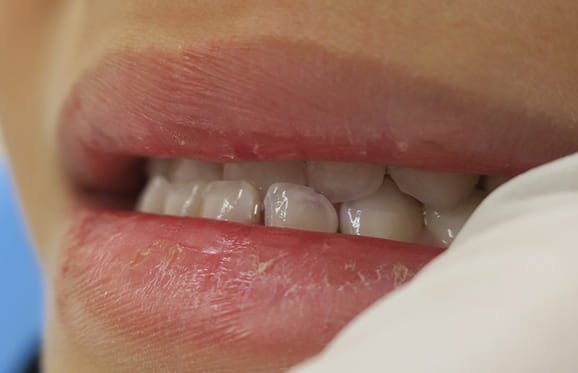

● 歯根が折れ保存不可の歯を抜歯して、そのスペースに八重歯を並べた症例

藤沢デンタルオフィスの虫歯や破折で抜歯後の部分矯正